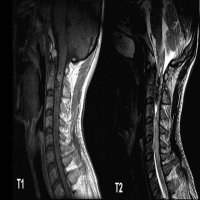

动静脉畸形(Arteriovenous Malformation, AVM)是一种先天性或后天性血管发育异常,表现为动脉和静脉之间直接相连,绕过了正常的毛细血管网。这种异常连接会导致局部血管结构紊乱、血流动力学改变,可能引发出血、疼痛、器官功能障碍等并发症,...